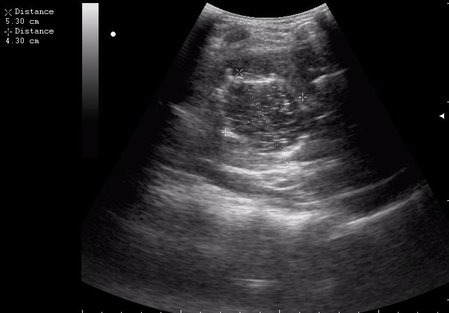

17-летняя девушка с множественными поражениями печени

Вложения

2.JPG